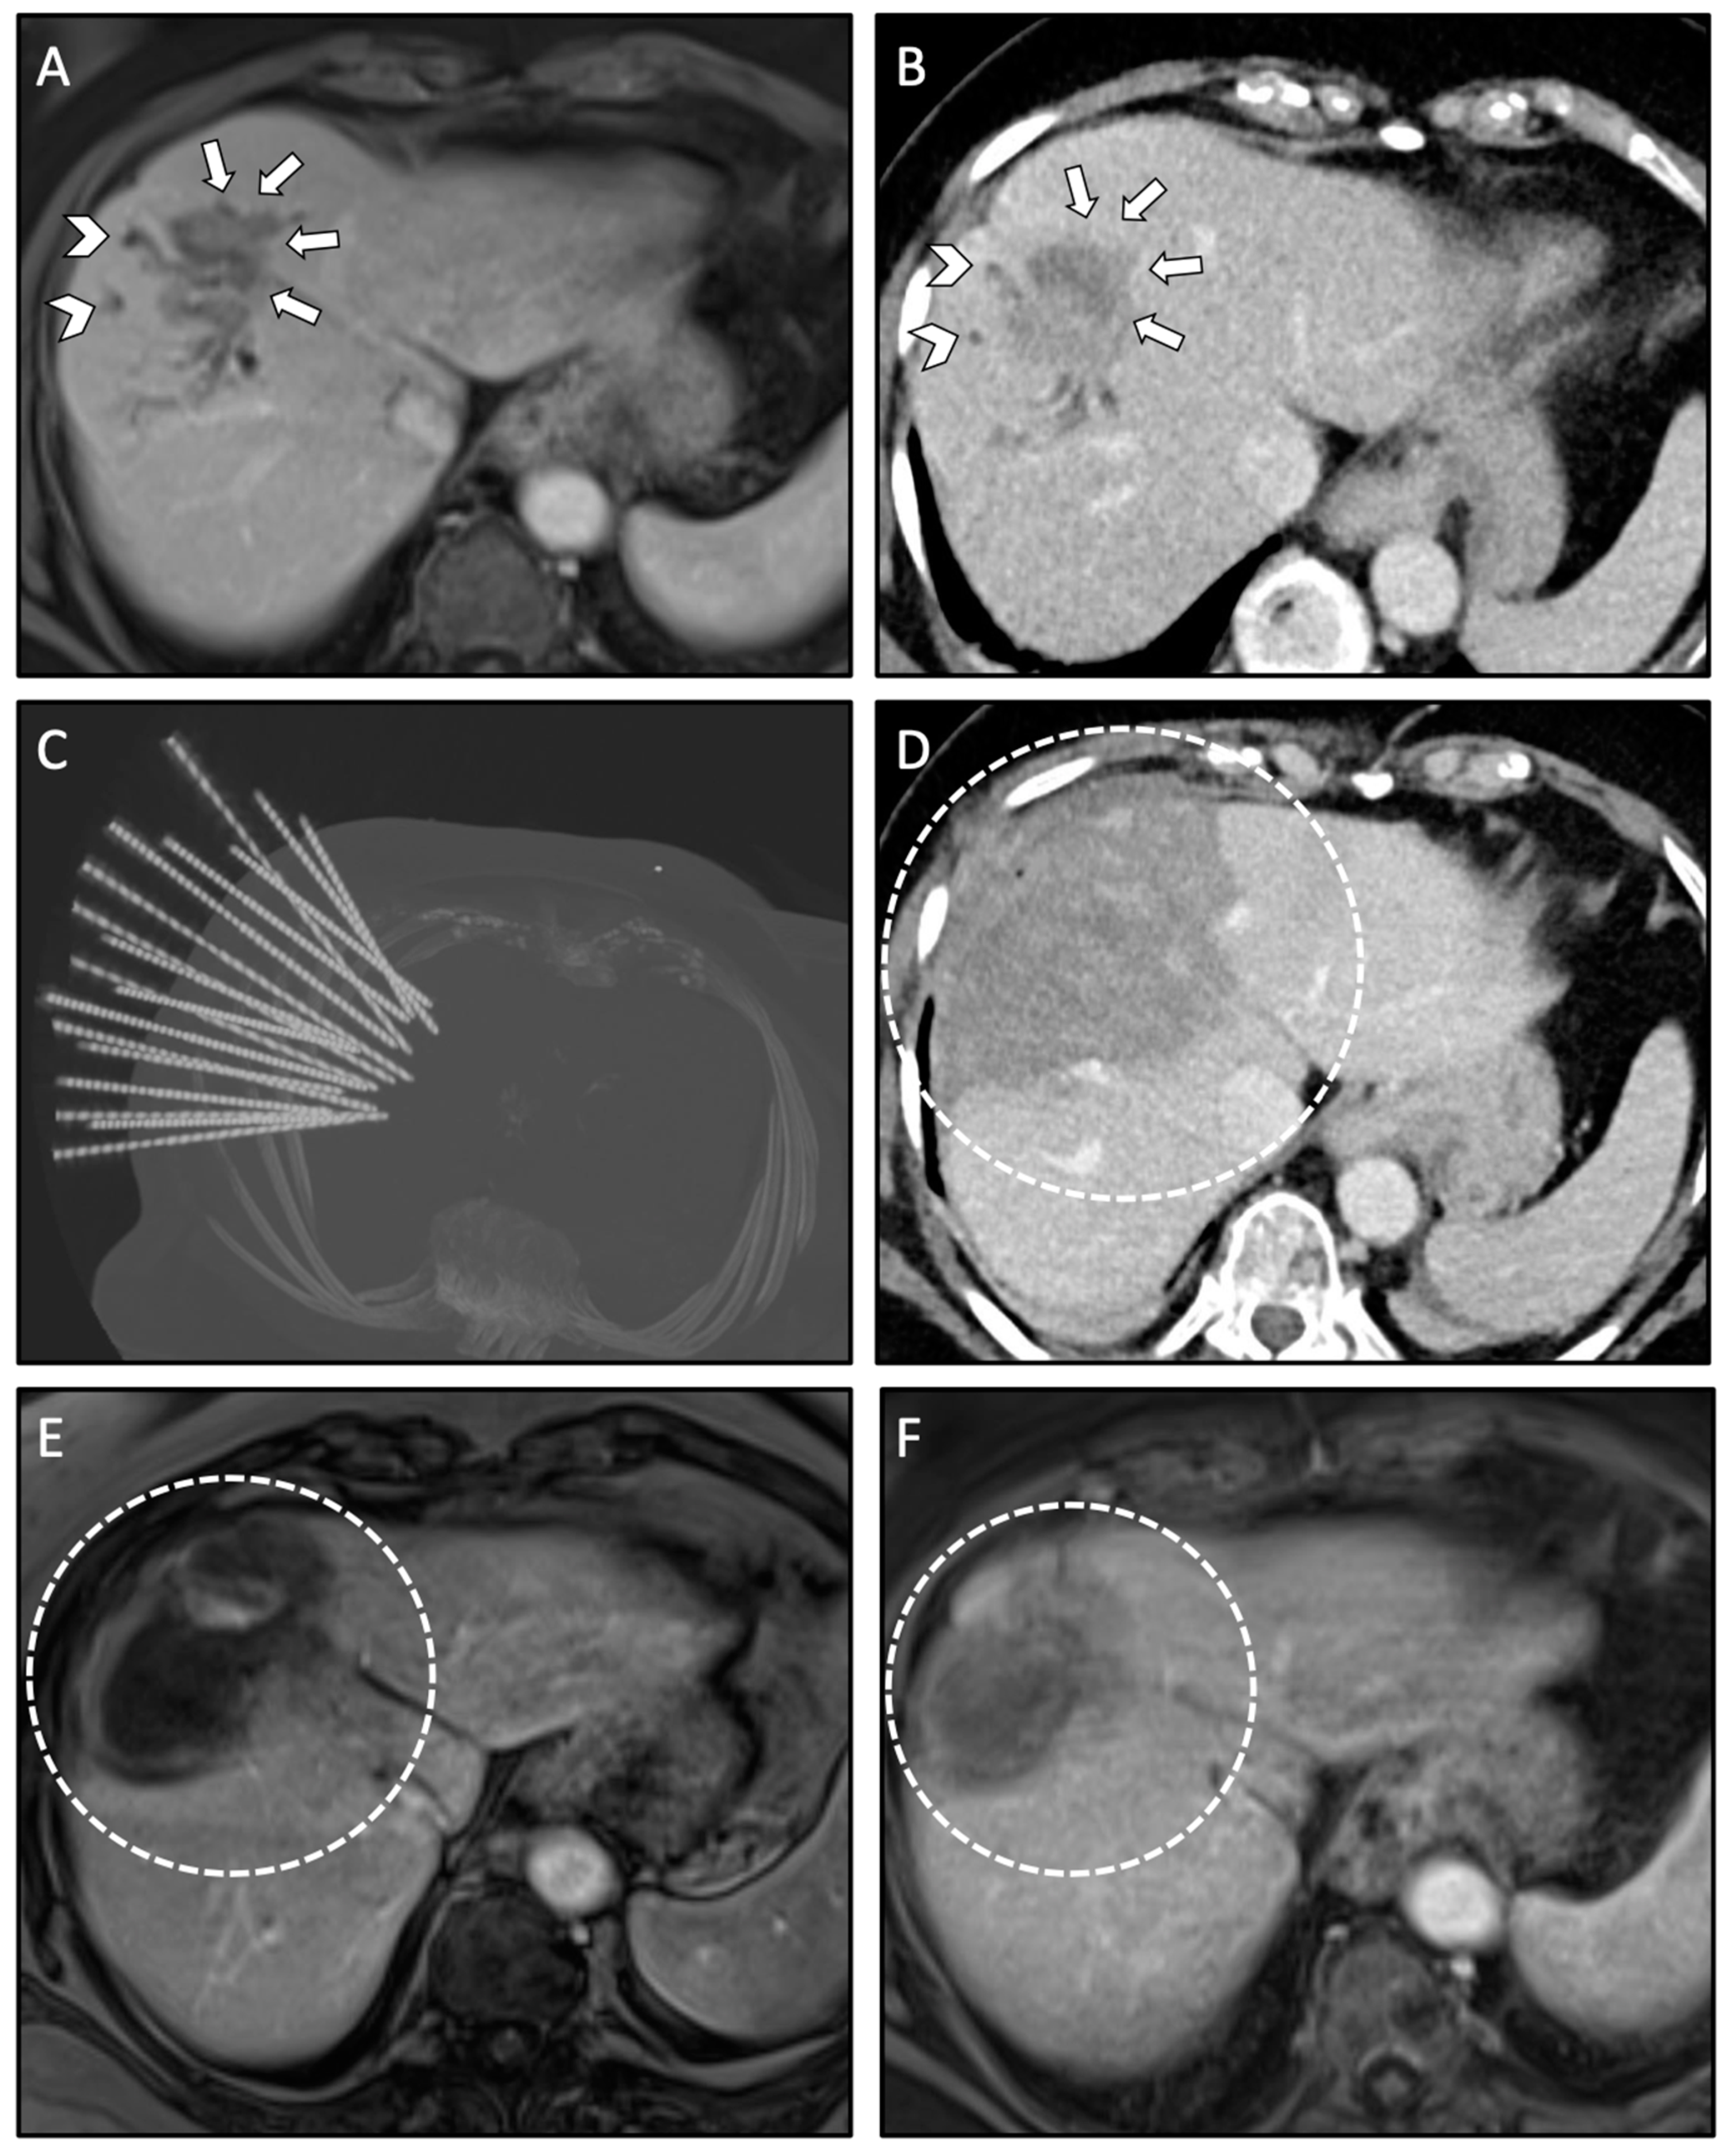

Using coaxial needles as guidance for the ablation probes has several advantages: the coaxial needles (placed before ablating) remain in the planned position relative to the tumor even after tissue shrinkage; large ablation areas can be achieved by placement of multiple coaxial needles. Coaxial needles are less space occupying as compared to ablation probes. This is especially relevant for heavy patients with limited space in the CT gantry; it is financially sustainable, as only up to three RFA probes are required for a feasible serial ablation. Moreover, the use of coaxial needles allows to perform a biopsy of each tumor prior to the ablation. In addition, the use of coaxial needles allows for simultaneous treatment of multiple lesions (up to 24 liver metastases reported by the team in Innsbruck) and very large lesions (up to 18 cm in diameter reported by the team in Innsbruck) within one session. An example with multiple coaxial needles for SRFA is shown in Figure 2.

Figure 2.

Case of a 76-year-old female with local recurrence of CRLM after conventional US- guided RFA treated by anatomical ablation of liver segment VIII using 18 coaxial needles for SRFA. (A,B) Pre-interventional MRI scan (A) and planning CT scan (B) of the SRFA procedure with 45 mm recurrence of the CRLM (white arrows) and consecutive dilated intrahepatic bile ducts in liver segment VIII indicating cholestasis (white arrowhead). (C) Maximum Intensity Projection (MIP) of the non-enhanced control CT scan showing the position of 18 coaxial needles. (D) Final control CT scan after anatomical ablation with complete necrosis of liver segment VIII. (E,F) Follow-up MRI scan at 3 months (E) and 21 months (F) after SRFA, showing no evidence of LTP with shrinking necrosis zones (white dashed circle).